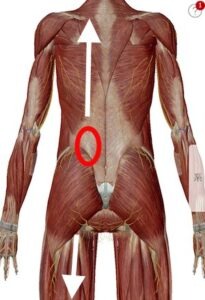

大腰筋が腰椎を圧迫

僕の経験による腰椎椎間板ヘルニアの本当の原因は大腰筋にあります。

この大腰筋ですが

主な役割:股関節を安定させる、歩く際に脚を挙げる働きをします。

起始停止:起始部は胸椎(T12)から腰椎(L1~5)の横突起で、大腿骨の小転子に停止します。

つまり足の付け根部分と腰椎を結んでいる筋肉なのです。

硬直した大腿部が大腰筋を下方向に引っ張ったり、大腿骨頭の位置ずれが起きて大腰筋が下方向へ強く引っ張られたり、大腰筋そのものが硬直した場合に 起始部として付着している腰椎1〜5の何れかに負荷をかけてしまい圧迫が起き、押しつぶされた軟骨が変形したり 飛び出したりするのではないか?とい仮説を元に大腰筋を補正する施術をした結果98%もの方々の痛みが消失しただけでなく、飛び出していた軟骨も元に戻ったのです。

大腰筋が下方向に圧力をかけ椎間板が変形や飛び出しを起こす。

まずはこちらの図。大腰筋ですがこのように腰椎から足の付け根部分に接続されていますので、長時間座っていたり、立ち仕事の長い方、立ったりしゃがんだりを繰り返す方には負担が大きく硬直して縮むことで腰骨を足の方へ(下方向)引っ張ると先程説明しました。

大腰筋が硬直

硬直した腰筋が縮んで腰椎を下方へ圧迫

そしてもう1つ。腰椎(腰骨)の同じ部分に多裂筋という背骨に沿った筋肉も付着しています。

多裂筋に硬直により上と下に引っ張り合う

硬直した筋肉は固くなり縮む習性がありますので、多裂筋の硬直により背中が凝る(固まる)または上方向に腰椎を引っ張る状態が発生します。

この状態で大腰筋が硬直すると大腰筋が腰椎の付着部分を下方向へ引っ張るので多裂筋と上と引っ張りっこになり間の椎間板が耐えられず飛び出してヘルニアになるのです。

下の図のように腰の筋肉は骨盤だけでなく足や背中、腕にも繋がっています。その為、腰だけを診る治療法や骨盤の歪みだけを診る治療法や筋膜、骨格などを主に診る治療法では見落としてしまう部分があり、それがヘルニアの腰痛がなかなか治らない原因の1つにもなっています。

毎日のお仕事や家事などで披露が蓄積すると筋肉は硬直し縮んで黄色い矢印の方へ引っ張る力が生まれます。腰を中心に上にも下にも引っ張られることで、骨盤に歪みが生まれたり腰椎を圧迫してヘルニアになったりします。

この図のように腰に連携している筋肉は多数あり、それらの筋肉が硬直して縮むことにより筋肉の末端が付着している骨盤などの位置にズレが生じ痛みを生み出しているのです。

例えばこの図のように背中や肩が張っていて動きが悪い状態の時に太ももが硬直して縮んだ場合には下方に引きずり込まれる形になり筋肉のズレが生じて骨盤までが歪んで腰に痛みがでます。

例えば肩こりや首コリが酷い場合に、長時間座っていたり、中腰や屈伸などの脚への負担が大きい場合には、この図のように上下に縮んだ筋肉が引っ張り合うので中間部分の腰に痛みが生じます。